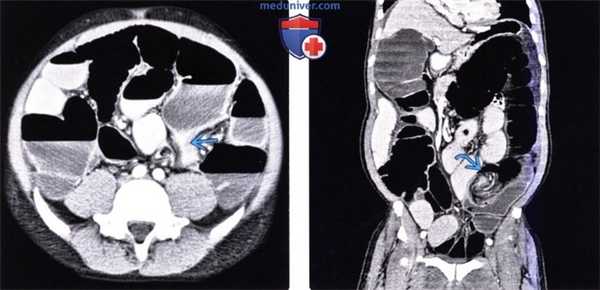

(Слева) На аксиальной КТ с контрастным усилением у мужчины 47 лет с жалобами на запор и отсутствие отхождения газов, у которого в течение шести дней сохранялось вздутие живота и боль, определяется заворот сигмовидной кишки в нижних отделах живота слева, при этом нисходящая петля перекрученной сигмовидной кишки имеет вид «клюва».

(Справа) На корональной КТ с контрастом у этого же пациента определяется характерное скручивание брыжейки на стороне заворота сигмовидной кишки.

о Симптом «клюва»: постепенное коническое сужение просвета петель кишечника до и после заворота

о Симптом «водоворота»: тугой перекрут брыжейки и кишечника возле основания заворота